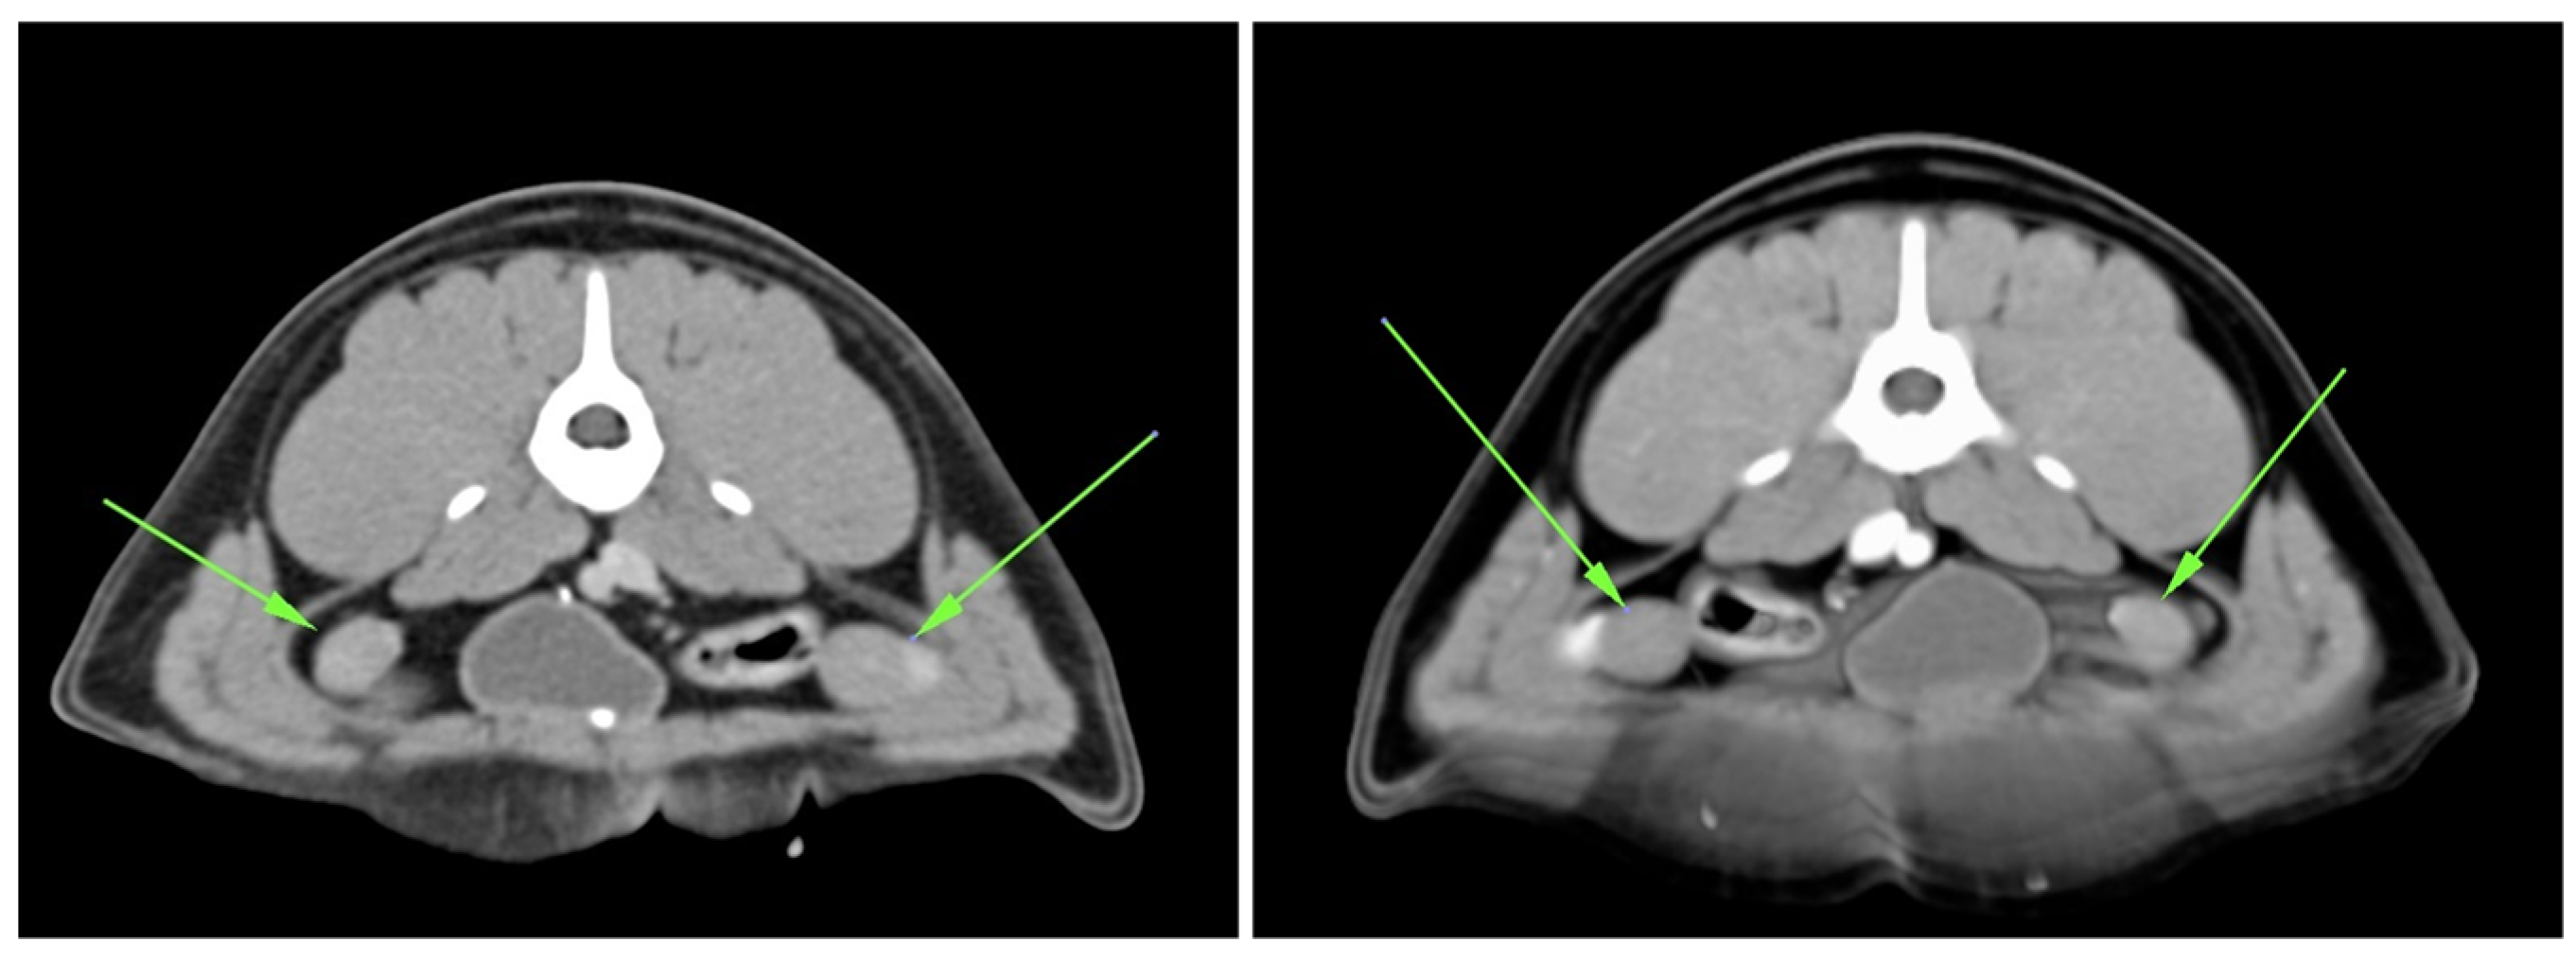

Additionally, imaging tests were performed using an Esaote MyLab Alpha device (Figure A2) and computed tomography (CT) (Figure A3). This advanced diagnostic examination was carried out on a multi-slice CT scanner (Sensation 16) with iodine contrast medium (370 mg/mL) at a dosage of 800 mg iodine/kg.

Figure A3.

CT images showing intra-abdominal testicular structures (green arrows).